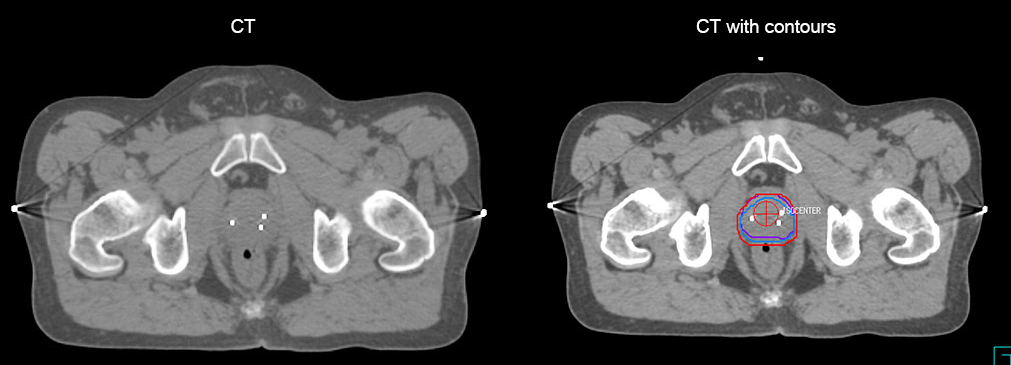

Impressive clinical benefits for prostate

“The biggest problem for CT-based planning, especially in prostate, is you can’t see the cancer very well,” says Dr. Stevens. “On CT it can be quite challenging to see the edge of the prostate especially at the apex. When the edge of the prostate can’t be delineated well on CT, radiation oncologists will increase their margins a little bit so they don’t miss it, but that can also increase toxicity.”

“Using MR, the prostate is well delineated. We quickly see the edges of cancerous tumors like in prostate cancer, and as normal structures can be defined, we can optimize the treatment plan to protect these organs and their normal function. This can potentially improve the outcome. And it improves workflow as well. We can contour more quickly, confident that the tumor is going to be in the field.”

Special requirements for MRI in RT planning

“There are some general challenges in RT imaging – even with CT – such as imaging geometry and positioning accuracy. Positioning is extremely important in RT, because we need reproducibility between imaging and treatment position. We also need accurate geometry so we can be sure our treatment plan is properly delivered during the treatment,” says Dr Yan.

“The Ingenia MR-RT configuration includes an external laser positioning system for patient alignment and a flat tabletop for imaging the patient in treatment position. Ingenia MR-RT also came with a special QA package for regular monitoring of precision. Our Ingenia 3.0T scanner achieves good geometric accuracy – within a millimeter for most patients – and the phantom measurement is even better,” he adds.